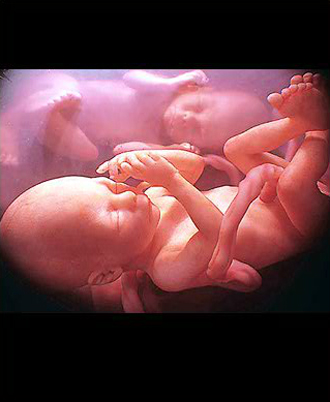

- 선택 검사 (16주~20주)

- 양수검사 (분만시 연령이 만 35세 이상, 기형 가족력이 있는 경우는 필수)

- 필수 검사

- 복부 초음파 (1회/4주)

- 중기 정밀 초음파

(태아 내부장기 및 근골격 기형 등을 검사)

※ 20주 이후로는 철분제 꼭 복용하세요.